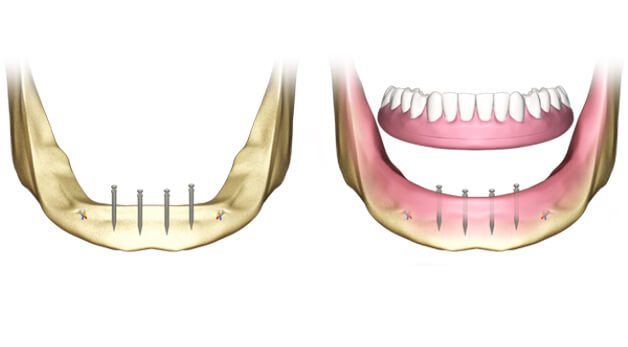

Мини-импланты

Корневидные модели маленьких размеров. Фиксируются в десне, не задевая костной ткани. Показаны при недостаточном объеме челюстной кости (если невозможно использование классических стержней), когда необходимо обеспечить дополнительную опору съемным протезам. Отличаются высокой приживаемостью, но серьезных нагрузок не выдерживают.

Базальные

Вживляются в глубокие (базальные и кортикальные) слои челюсти при недостаточном объеме кости. Имеют агрессивную резьбу и широкие лепестки у основания, что обеспечивает надежную фиксацию. Рекомендованы для замещения нескольких расположенных рядом зубов. Эффективно распределяют жевательную нагрузку и могут нагружаться протезом сразу после установки.